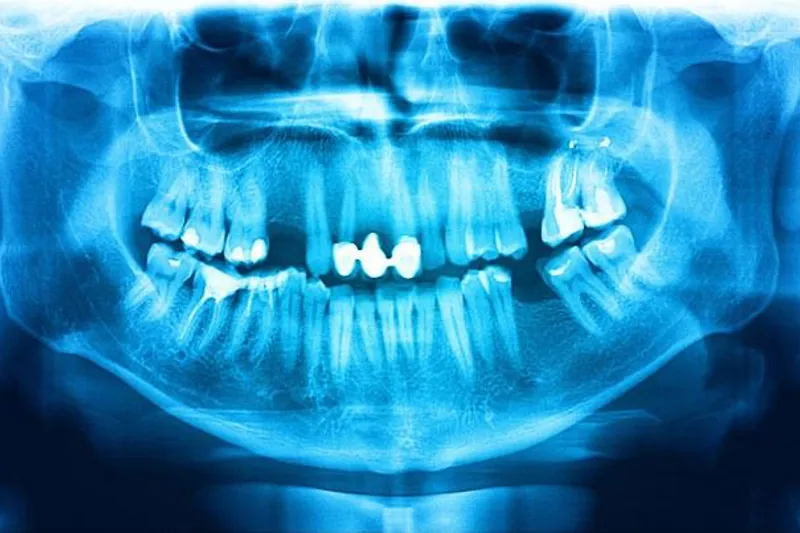

Græske forskere har udgivet en systematisk oversigt om indikationer for anvendelse af panoramaoptagelser inden for børnetandpleje. Kun 16 tidligere publicerede undersøgelser levede op til inklusionskriterierne, og de var fordelt på seks forskellige indikationsområder (caries, akutte infektioner, tandtraumer, dentale anomalier, udviklingsforstyrrelser og patologiske tilstande), så hovedkonklusionen blev, at der mangler primær forskning af tilstrækkelig kvalitet på området.

I forbindelse med cariesdiagnostik noterede man, at der registreres flere carieslæsioner ved klinisk undersøgelse end ved hjælp af panoramaoptagelse. I en kommentar til oversigten hæfter britiske forskere sig ved, at undersøgelsens resultater er i overensstemmelse med de britiske retningslinjer, som anbefaler en kombination af klinisk undersøgelse og bitewingoptagelser i forbindelse med cariesdiagnostik.

De påpeger endvidere, at panoramaoptagelser kun bør komme i betragtning ved diagnostik af traumer, infektioner og andre patologiske tilstande, hvis intraoral optagelser med lavere stråledosis ikke giver tilstrækkelig information til at danne grundlag for kliniske beslutninger.